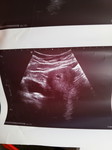

ปวดท้องน้อยแบบบีดๆแล้วมีเลือดออกมาตั้งแต่วันที่6 แล้วไปโรงบาลวันที่6ยังตรวจเจอถุงตั้งครรภ์ แต่หมอไม่ฉีดยากันแท้งให้ได้แต่ยาพารากลับบ้านค่ะ พอวันที่7ก็ยังปวดไม่หายเลยเปลี่ยนโรงบาลค่ะ แต่หมอตรวจอัลตราซาวด์แล้วไม่เจอถุงตั้งครรภ์ค่ะ หมอนัดตรวจอีกทีวันที่10ค่ะ จะมีโอกาสเจอถุงตั้งครรภ์มัยค่ะ ตอนนี้ใจไม่ค่อยดีเลยค่ะ